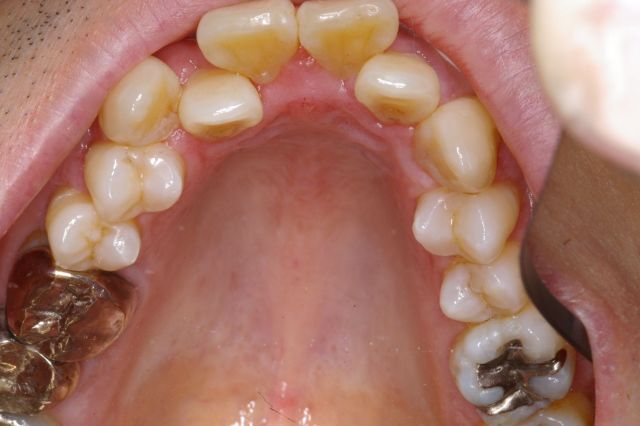

かなり重度の上顎前突症例です。 バードフェイス(鳥貌)と言われる横顔で、以前(2000年頃まで)は矯正不可能と言われていた症例ですが 矯正用インプラント(矯正用ビス)を入れることにより、短期間で改善できた例です。 尚、矯正用インプラントは、力がかかる時だけ入れるもので使用後は簡単に外せます。 矯正用インプラントは、2000年頃より日本に導入された治療法です。(詳しくは、コチラ) もちろん、矯正用インプラントを使用しなくても治る症例も沢山あります。 |

上顎の歯槽骨までも後ろに後退させて側貌も改善されています。(顔は伏せています。) 歯並びだけではなく、顔の見た目も改善することが矯正の目標と考えています。 また、歯列もV字型の咬み合わせからU字型になって咬み合わせも良くなり、口元の審美性も改善されています。 |

| また、矯正期間をかなり短縮できる利点があります。 矯正期間1年6カ月 欠点は、インプラントを埋めることですが、小さなビス(長さ8mm直径1.8mm程度)なので簡単に出来ます。 また、インプラントを除去後は、粘膜、骨は完全に元に戻りますので心配いりません。 |